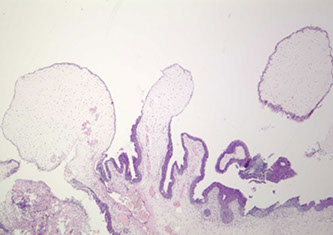

Inverted papilloma

Rare, b9 urothelial tumor, presents c hematuria and irritative sx

- 7M.1F, usually ~50 yo

- usually trigone and bladder neck

- b9 and not related to urothelial carcinoma

• Most commonly seen in the trigone region

• Usually solitary (3%

• Polypoid /sessile on cystoscopy , smooth surface

• Size: wide range

• Can be associated with urothelial carcinoma, yet not

thought to be directly related

Micro: smooth surface covered by normal urothelium and endophytic growth of urothelial cells aroborizing extensively from surface urothelium to lamina propria

- anastomosing cord, columns and thin trabecula

- peripheral pallisading with spindly nuclei

- no atypia or mits

- no exophytic component

- may see squamous morules

- may show non-keratinizing squamous metaplasia

DDx: inverted urothelial carcinoma

Inverted Papilloma Comparison to Urothelial Carcinoma

• Lacks cytological atypia

• Mitotic activity limited to basal cell layer

• Lacks inflammation and reactive stroma

• Squamous metaplasia lacks keratin formation

• Lacks muscularis propria invasion

Px: recurrence ~1%